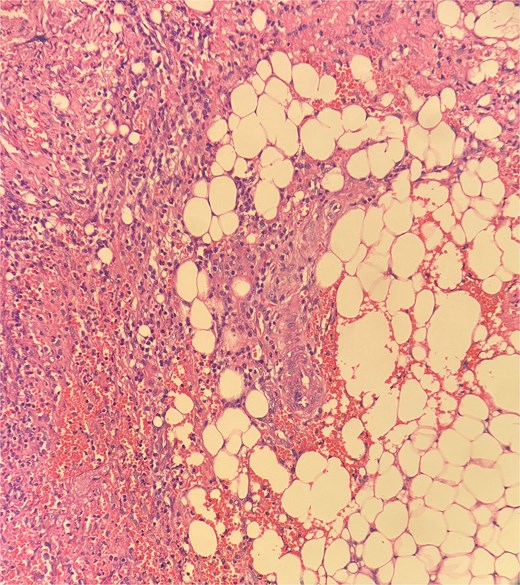

The patient underwent examination under anesthesia and exicision and biopsy (Fig. 4) of the extra-luminal growth via perianal route under spinal anesthesia. A curvilinear incision was made in the right perianal region from 7 o’ clock to 11 o’clock position, 1 cm away from the anal verge to access the tissue, which was then excised in toto and sent for histopathological examination. The cavity was left open to heal by secondary intention. Histopathological examination (Figs 5–7) which was a definitive diagnosis revealed features suggestive of panniculitis. This was the key diagnostic test, confirming perianal panniculitis rather than a fistula or malignancy.

Picture depicting evidence of fat necrosis in the excised perianal tissue.

Sections show a dense inflammatory infiltrate within the subcutaneous adipose tissue, consistent with panniculitis. The infiltrate is composed of neutrophils, lymphocytes, plasma cells, and histiocytes.

Histopathological examination showed ghost-like adipocytes and foamy histiocytes.